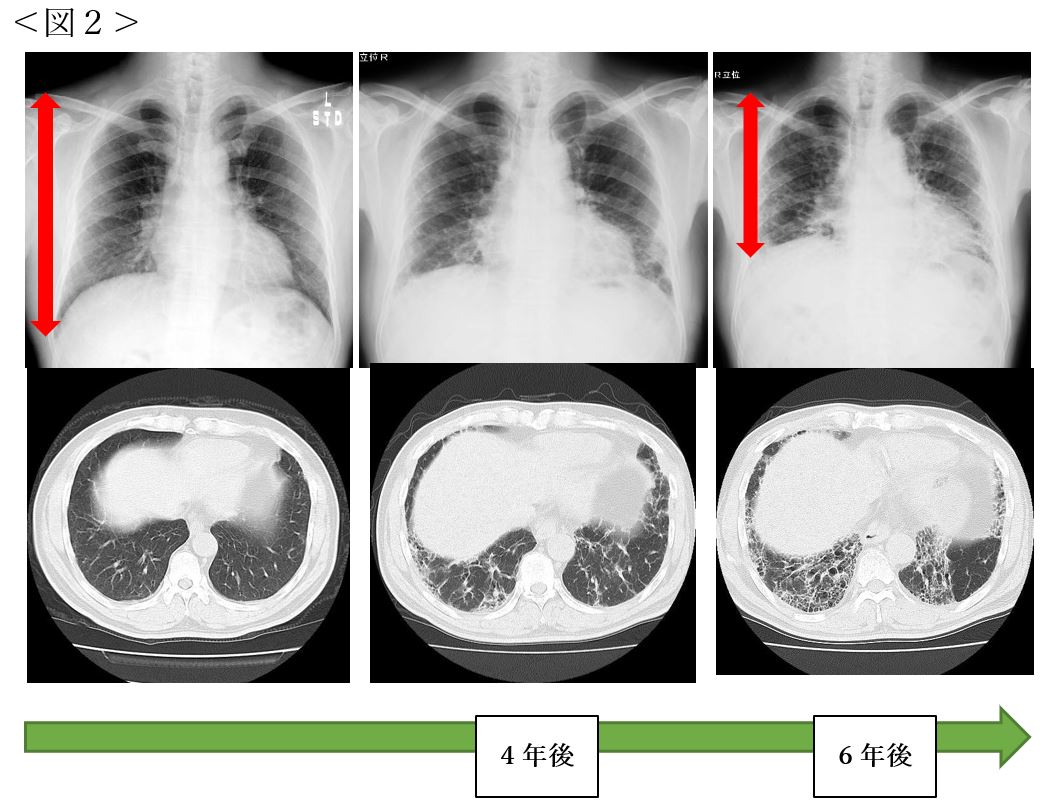

通常、毛細気管支炎が疑われる場合は、胸部聴診やレントゲン検査で診断します。原因菌がRSウイルスかどうかを確認するために、鼻水を採取して検査したりもします。 毛細気管支炎の治療法